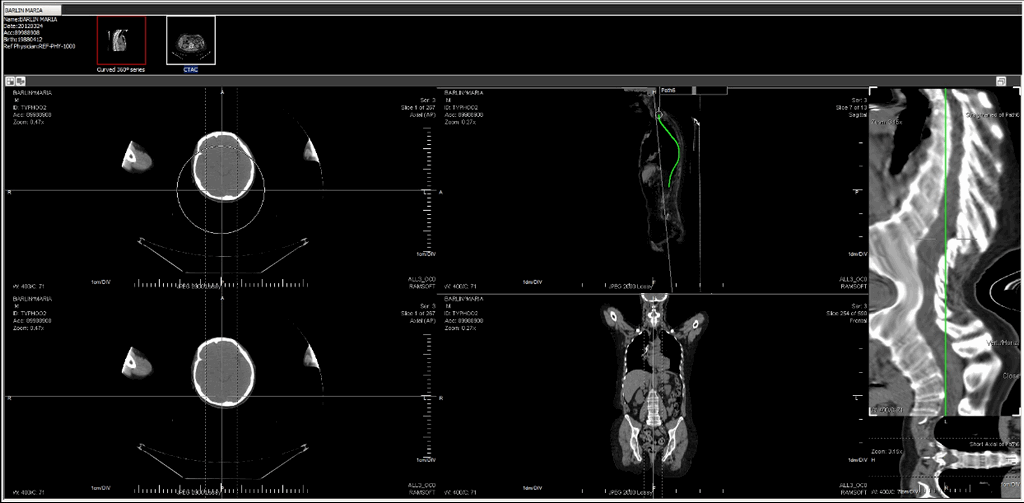

Extracting a cross-section MPR by straightening the path

Choosing the Straighten path and Display in Cross Sectional Window option straightens the path and creates a Cross-Sectional extract. After choosing this option, a cross section MPR displays the area chosen by the Path line (green line) in a separate Viewport next to the image.

It is possible to find the specific measurements of a specific section of the straightened out path. This is a three step process which is done by pressing the left Ctrl key and double-clicking the left mouse button on the scale to create reference points.

Clicking and dragging the mouse over the cross sectional MPR will allow the viewer to see the slices as per the tolerance level.

If you opt to slide the mouse over the straightened out path (which might be in Sagittal view), the bottom section will display that particular cross section slice in another view e.g. axial.